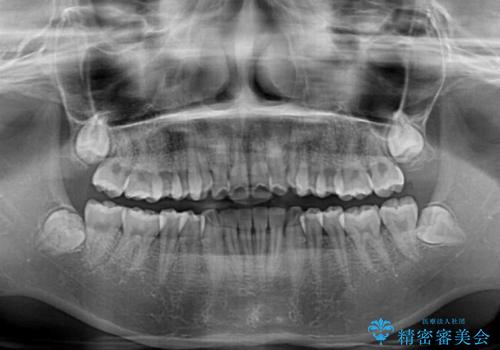

奥歯の咬み合わせを見ると、片方は上顎が下顎に対して相対的に前方にある状態でした。

咬み合わせを改善するためには、上顎臼歯を後方に移動させた咬み合わせにする必要があります。

インビザライン単体で改善することも可能ですが、ディープバイトのためインビザライン単体で達成する可能性が低いと考えられたため、カリエール・ディスタライザーという補助装置を併用して、より確実性を上げることとしました。